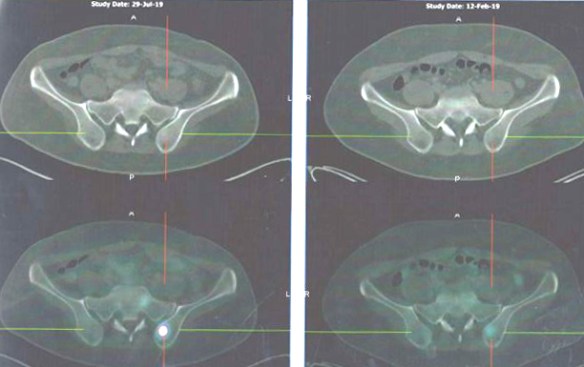

- PET scan on 14 September 2023 showed more serious condition.

- The metabolically active left lung mass with multiple neck, axillary and mediastinal nodes. Left pleura and bone lesions are likely due to primary lung malignancy.

- However, metastatic breast cancer recurrence cannot be excluded.